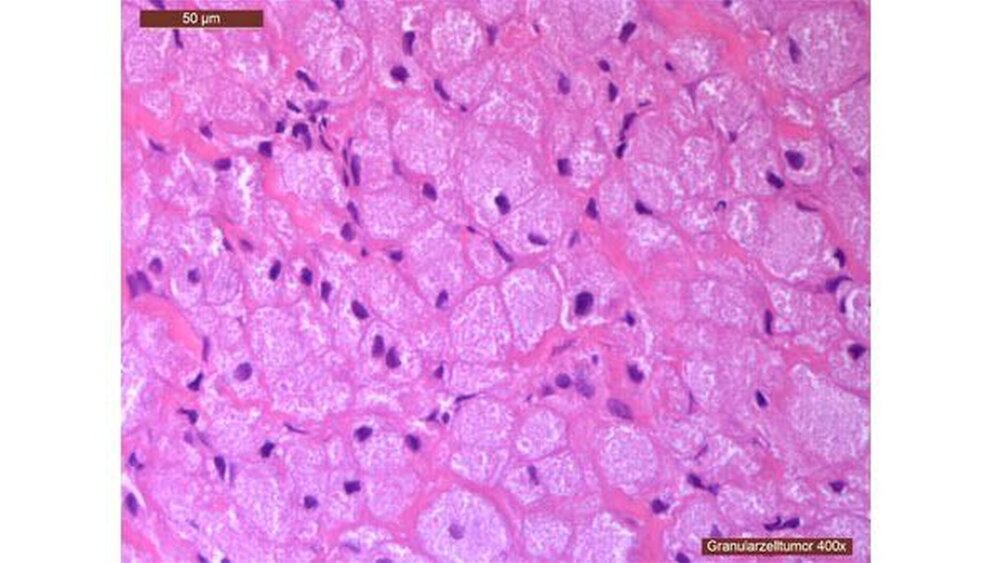

In der histologischen Auswertung (Abbildungen 3 und 4) fand sich ein regelhaftes, teilweise verhornendes bis hyperplastisches Plattenepithel. Ebenfalls wurden floride Ulzerationen innerhalb der Präparate festgestellt. Es zeigten sich Proliferationen von großen, ovalen Zellen mit parazentral gelegenen kleinen, runden Zellkernen sowie eosinophilem, feingranuliertem Zytoplasma. Dazwischen lagen zum Teil dilatierte, dünnwandige Blutgefäße, deren Endothelien unauffällig waren. Histopathologisch entspricht das dem Bild einer kongenitalen Epulis.